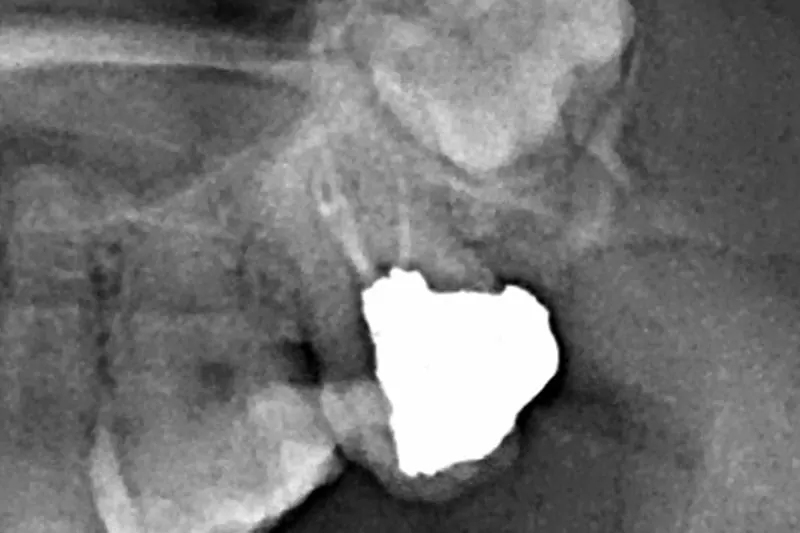

治療前X光片

我的牙醫師-沈庭帆醫師,是位可愛又幽默的媽咪,非常詳細為我解說目前牙齒的狀況,並分析上一次根管治療未成功的問題,牙齒為了做完假牙後能安心使用,根管勢必重做治療,而這次的根管治療有別以往的經驗,是採用顯微根管治療,透過顯微鏡精準醫治,能夠完整填補神經取出後缺口,不讓細菌有孳生的空間,針對二次根管治療或是細微難找的根管,盡到最大辦法醫治,是非常進步的醫療技術。因為醫師透明化治療解說,讓我對療程不會有未知的恐懼感,反而能更寬心治療。另外療程的安排及費用,也都有櫃檯小姐清楚的說明及同意書簽名,確保我非常了解自己的療程,避免後續產生不必要的疑慮。